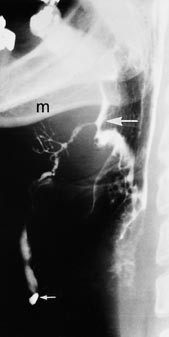

Ved undersøkelse fant man arrforandringer med keloiddanning på høyre side av halsen etter tidligere operasjon. Man kunne klemme ut klar væske fra en fistelåpning i midtlinjen ved thyreoideabrusken. Det var ingen synlig fistelåpning ved foramen cecum. Fistulografi viste kontrastfylling fra åpningen på huden med kommunikasjon til foramen cecum og kontrastovergang til svelget. I munngulvet fant man et grenet spyttkjertelliknende gangsystem (fig 1). Sialografi av begge glandulae submandibulares ble utført for å utelukke kommunikasjon mellom disse spyttkjertler og det gangsystemet som tømte seg i ductus thyreoglossus. Sialografien viste ingen slik kommunikasjon. Thyreoideascintigrafi viste lett asymmetri, med normal funksjon og beliggenhet.

Pasient 2. 14 år gammel jente med ca. ni måneders sykehistorie som startet med en kul i midtlinjen på halsen. Det tilkom etter hvert infeksjonstegn, og det ble gjort incisjon og drenasje. Etter dette utviklet pasienten en sinus med kronisk sekresjon og granulasjonsdanning omkring sinusåpningen. Hun ble på ny operert fem uker senere. Man fjernet en del bløtvev, men på grunn av vanskelig tilgang og uvanlig forløp av cysten ble det ikke foretatt ytterligere inngrep med fjerning av tungebein. Det tilkom ny sinusdanning og sekresjon. Det var ingen synlig fistelåpning svarende til foramen cecum. Sinografi viste kontrastoppfylling fra åpning i huden til et område opp mot foramen cecum. Gangen forgrenet seg her i et spyttkjertelliknende gangsystem med tilsvarende funn som i figur 1, men uten gjennomgående kommunikasjon til munnhule/svelg. Thyreoideascintigrafi viste intet patologisk.